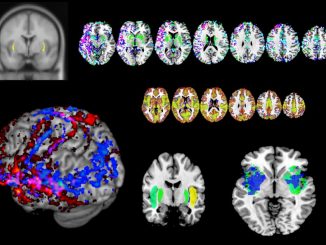

A brain area thought to impart consciousness instead behaves like an internet router, says study

11.14.2022

Tucked underneath the brain’s outer, wrinkly cortex is a deeply mysterious area, known as the claustrum. This region has long […]